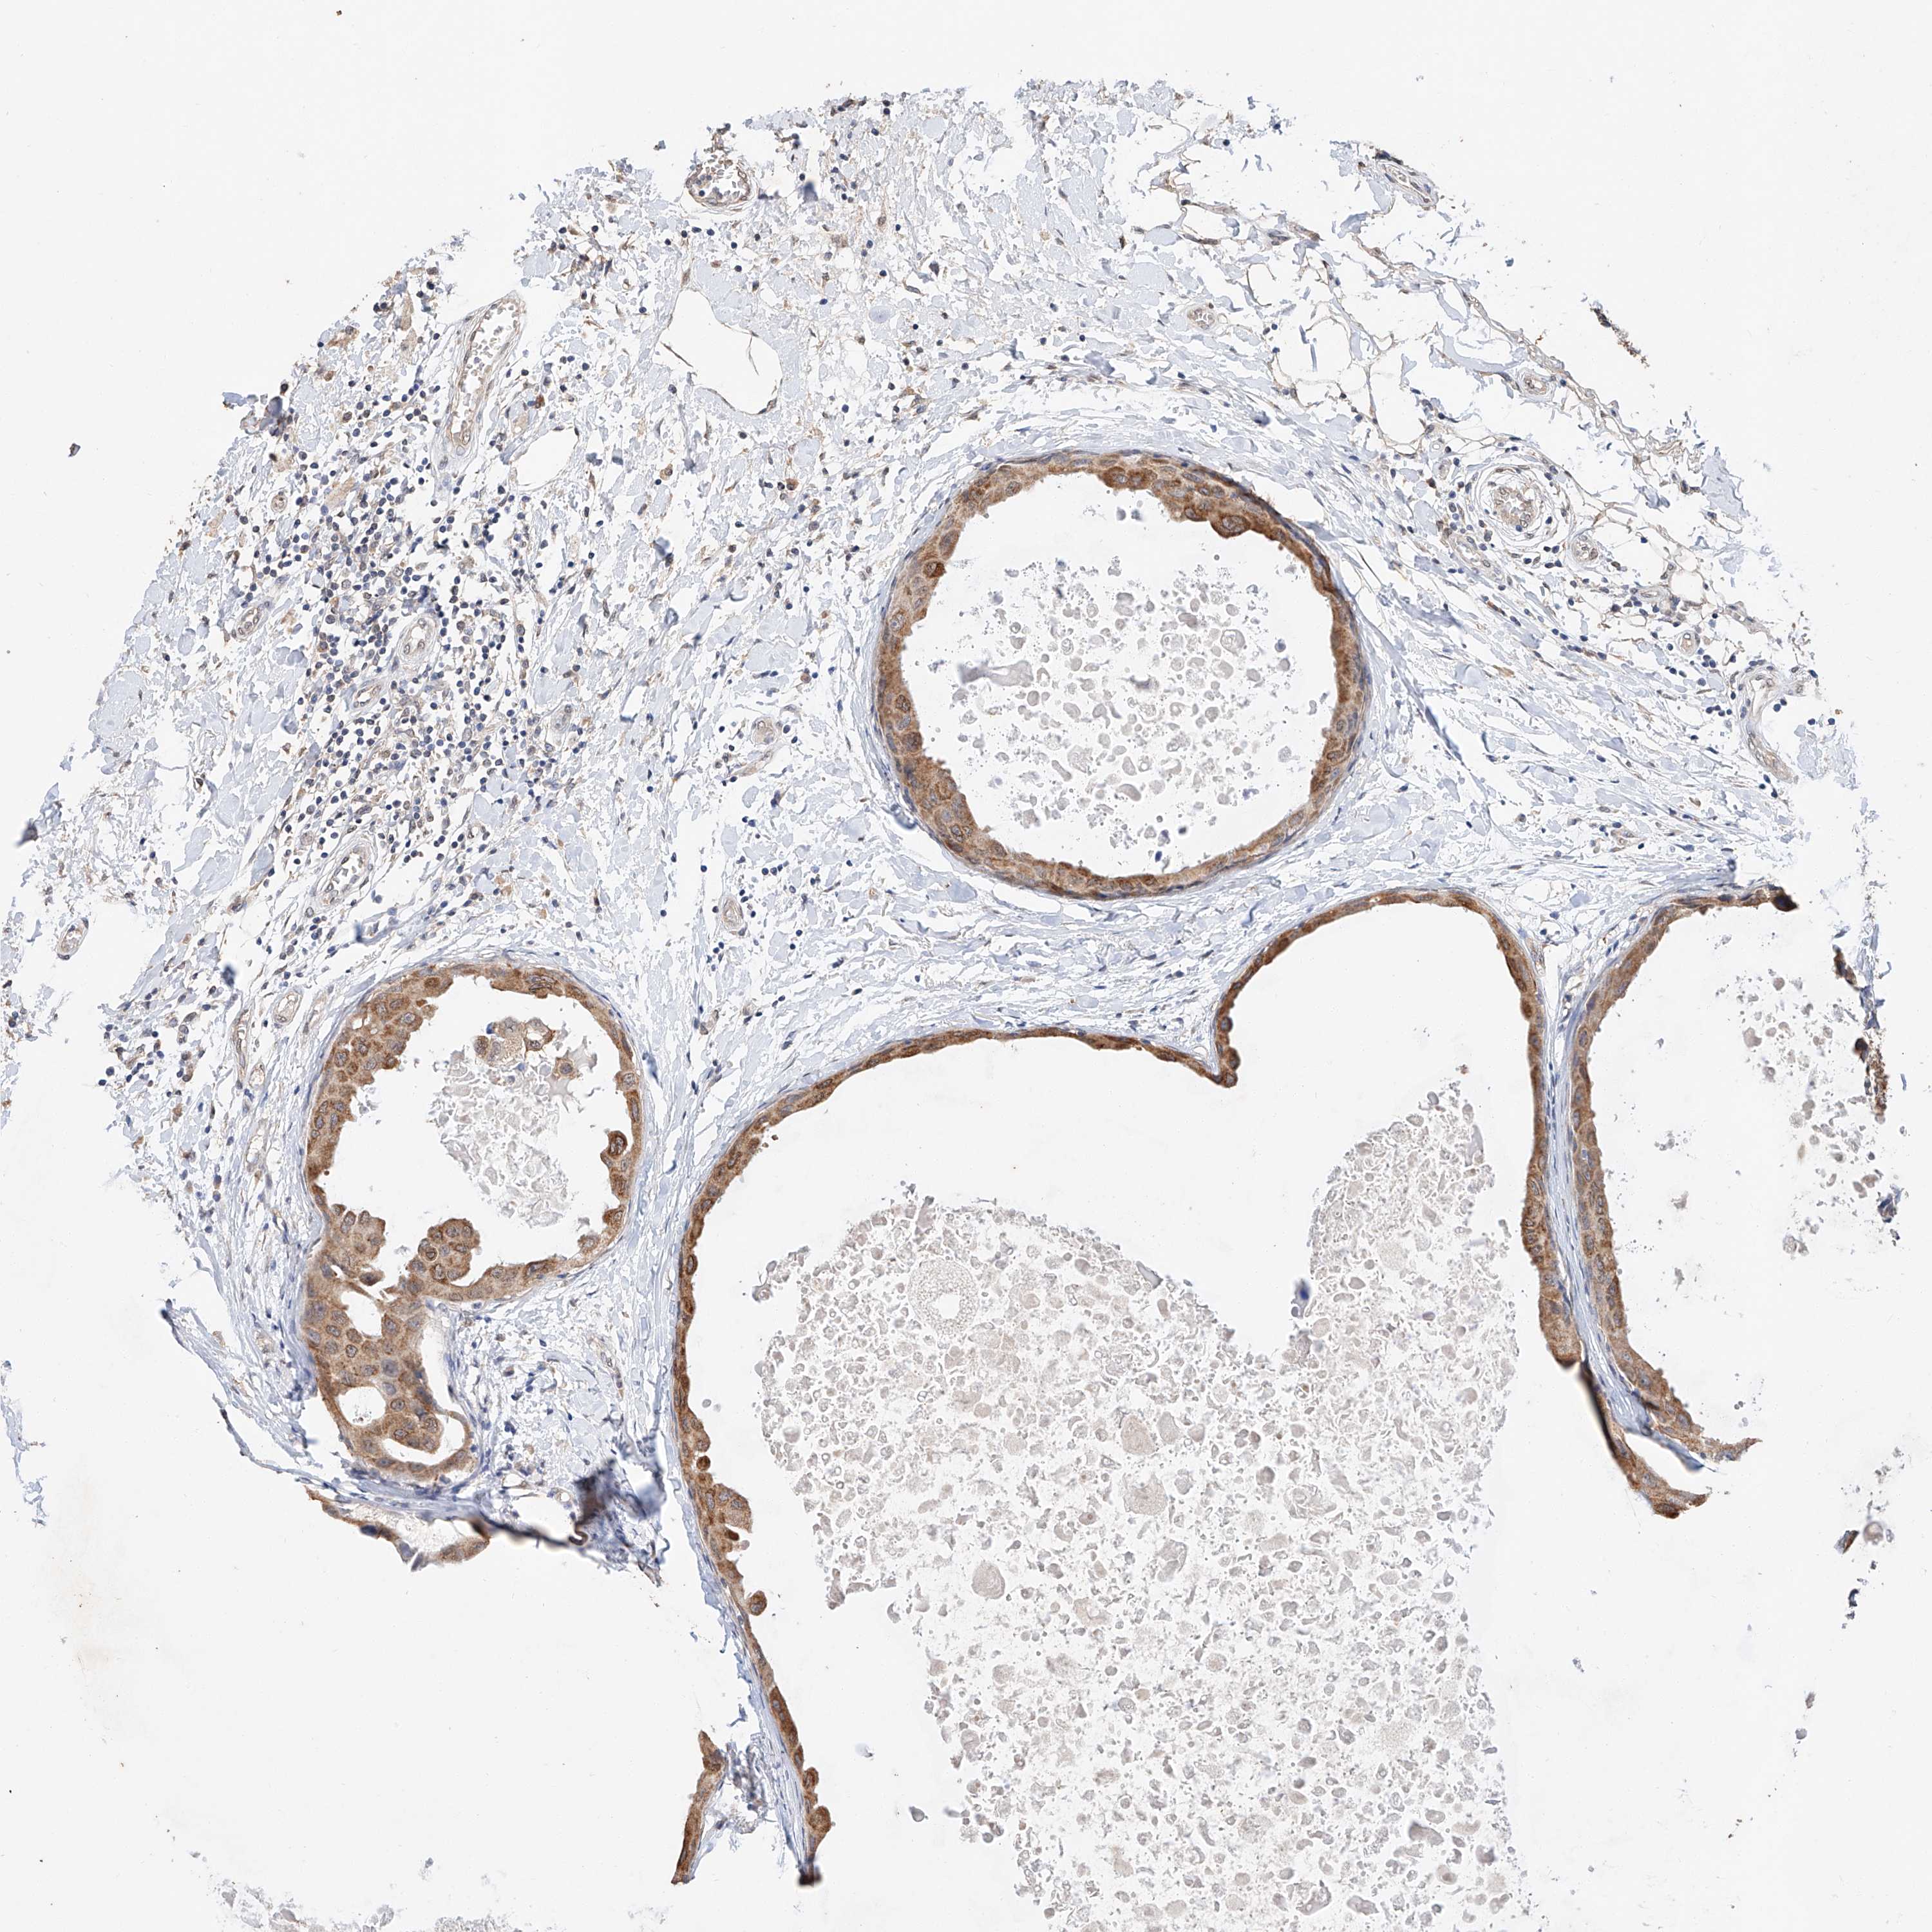

CANCER BREAST CANCER Show tissue menu

BRCA TCGA BRCA VALIDATION PROTEIN EXPRESSION